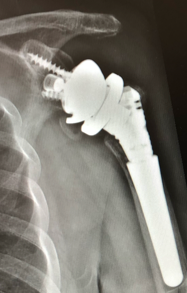

6-month follow-up

Implantation of the Link Embrace

- RSA

- Modular Revision Stem, 75 mm, cementless

- Proximal Body height 45 mm

- Humeral Reverse Tray, neutral

- Eccentric Glenosphere ø 36 mm with PE-Insert height 0

- Reverse Glenoid Baseplate with 2 compression screws and 1 locking screw